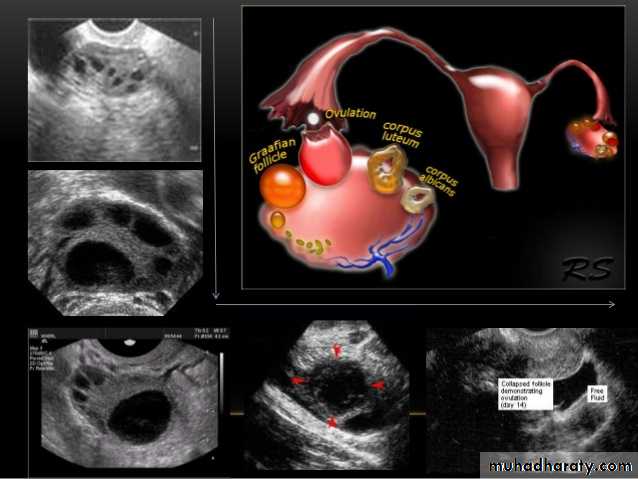

Ovarian cysts are commonly encountered in gynecological imaging, and vary widely in etiology, from physiologic, to complex benign, to neoplastic.Small cystic ovarian structures should be considered normal ovarian follicles unless the patient is pre-pubertal, post-menopausal, pregnant, or the mean diameter is >3.0 cm

Radiographic features

Ultrasound is usually the first imaging modality for assessment of ovarian lesions. Simple ovarian follicular cysts are:

anechoic

intraovarian or exophytic;

have an imperceptible wall

Polycystic ovarian syndrome (PCOS) is a chronic anovulation syndrome. Sonographic findings alone are not specific, and the diagnosis is made on the combined clinical, biochemical and sonographic grounds

Ovaries

may show sonographic features of polycystic ovariesbilateral enlarged ovaries with multiple small follicles: 50%

increased ovarian size (>10 cc)

12 or more follicles measuring 2-9 mm

follicles of similar size

peripheral location of follicles: which can give a string of pearl appearance

hyperechoic central stroma

the ovarian outline may be slightly irregular